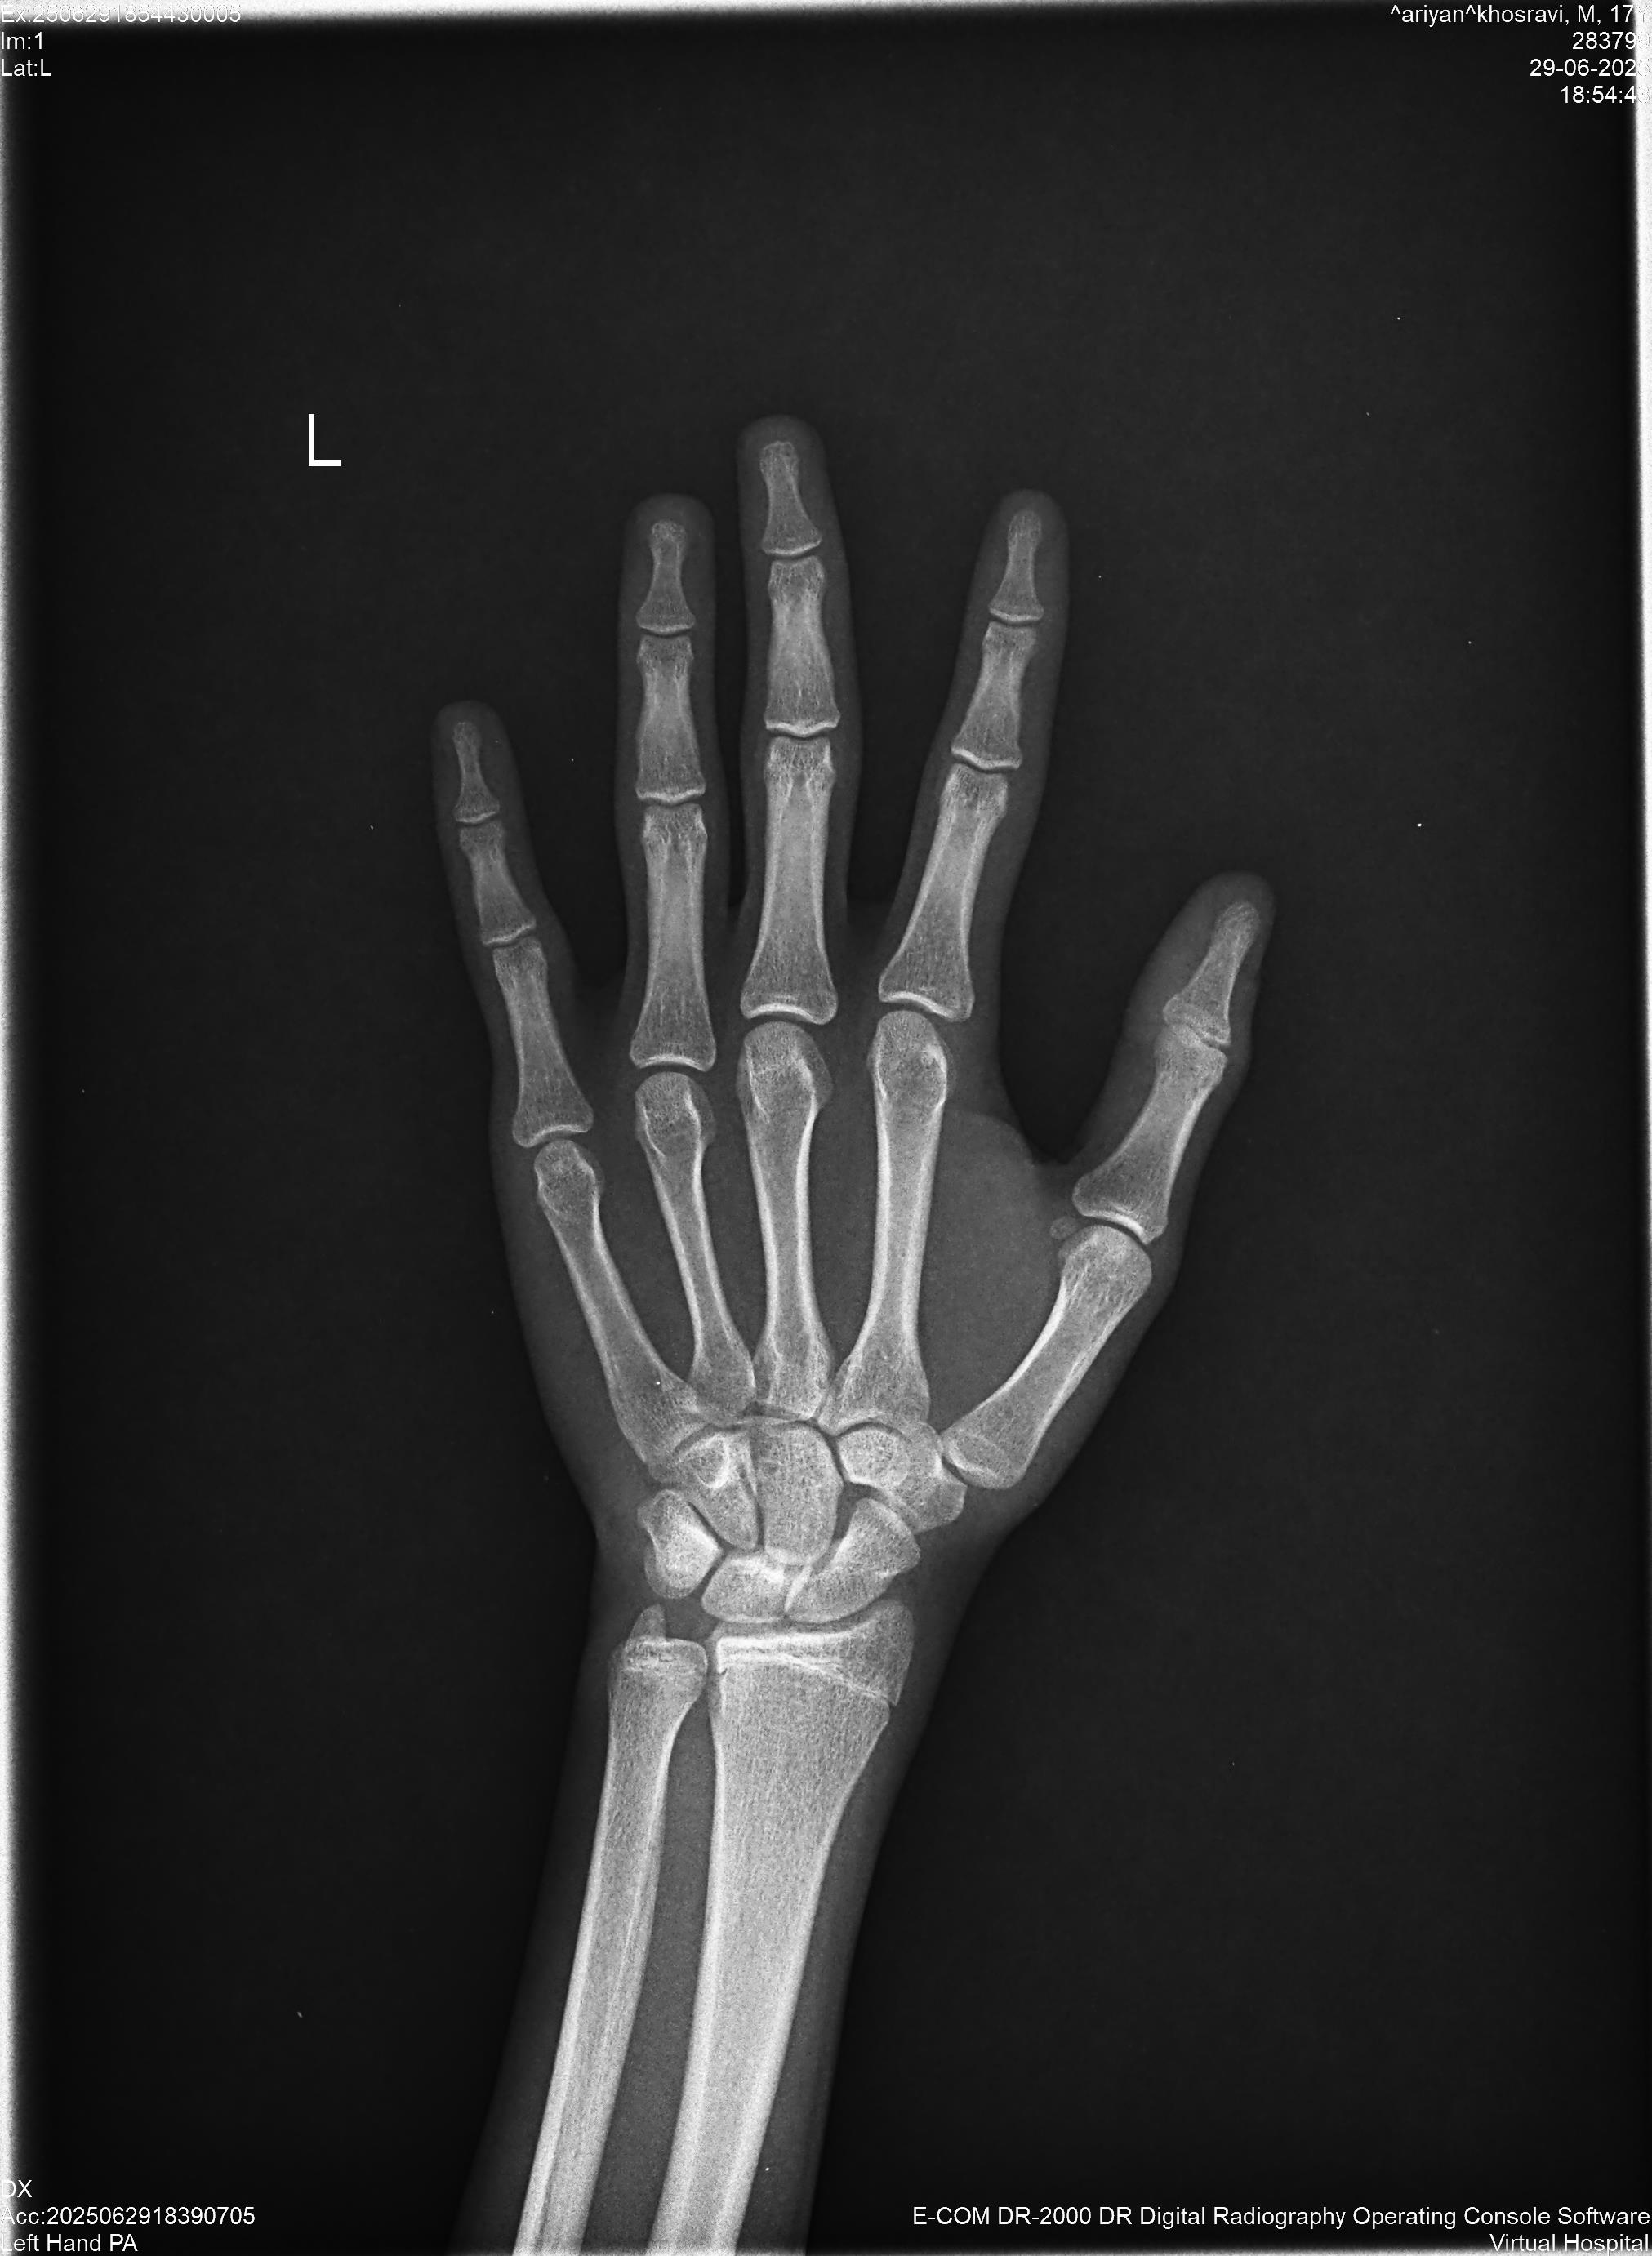

ممد سن : 18 وزن : 57 قد : 175

سلام وقت بخیر. صفحه رشدم بازه؟ اگه مچ دست بسته بشه بقیه هم بسته میشن همزمان با دیرتر بسته میشن؟ آخه میگن مثلا ستون فقرات دیر تر بسته میشه.